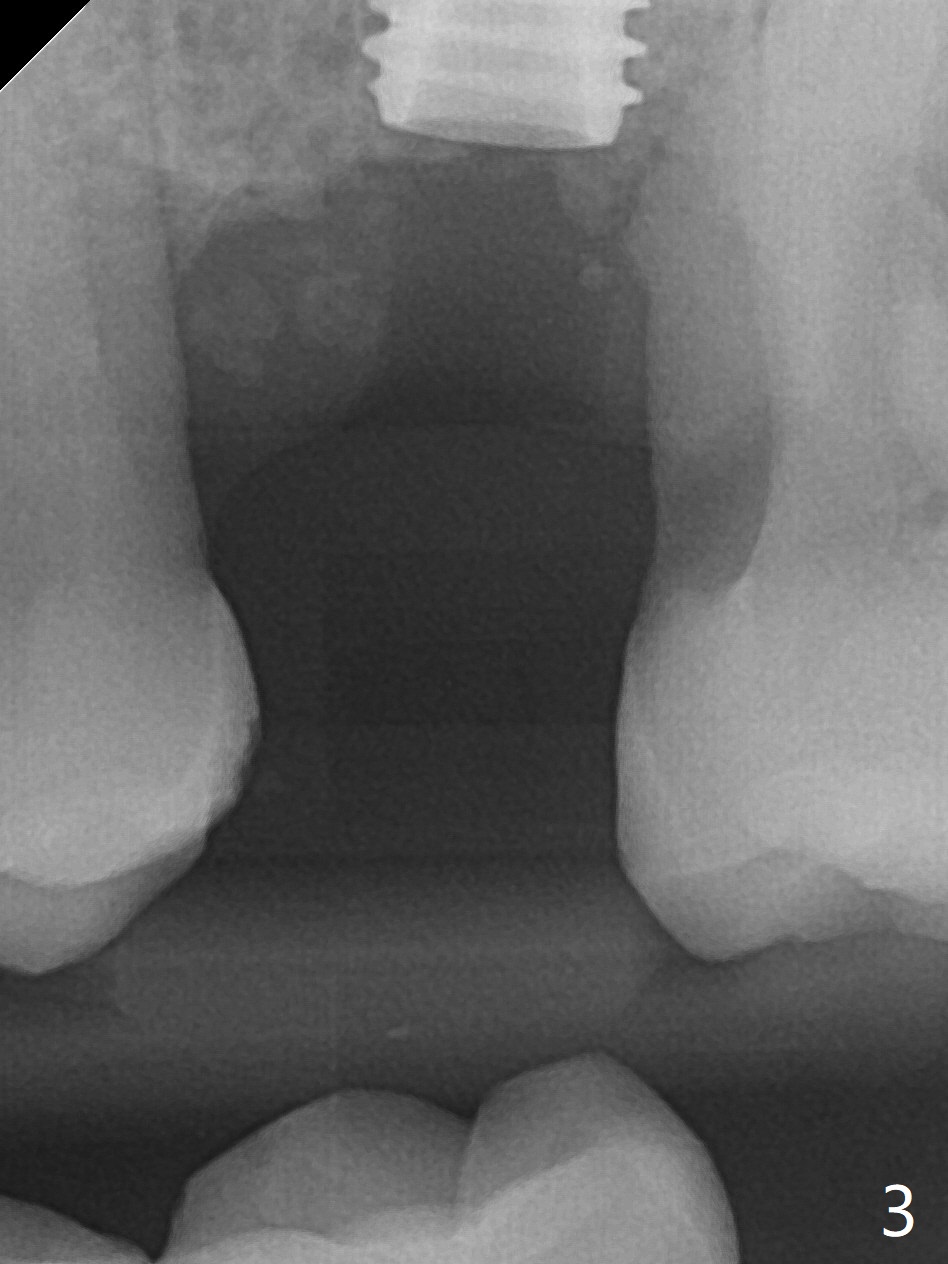

The patient is extremely nervous about implant placement at #14. Access is obtained with a 4 mm tissue punch, which appears to be the least traumatic. Since the gingiva is ~ 5 mm thick, vision is poor and it is difficult to change osteotomy buccally. It seems a 6 mm tissue punch is more appropriate for this case. The initial osteotomy depth is 14 mm (Fig.1). Since the tooth #15 is nonsalvageable because of furca caries and bone loss (Fig.1 *), the distal osteotomy at #14 is apparently acceptable. When a 5x13 mm implant is placed with >50 Ncm (Fig.2), the implant is subcrestal clinically except palatal (osteotomy not buccal enough), which is consistent with bitewing view (Fig.3). A 5.5x5 mm healing abutment is placed. Surprisingly the fearful patient does not experience any pain. Tissue punch is an atraumtic measure. A larger one (6 mm) allows more room to change osteotomy. The access can be closed with larger healing abutment. If this implant fails due to periimplantitis, it is due to palatal placement with too large the implant (5 mm vs. 4 mm at #3). Palpate the bone prior to changing next large drill when performing a flapless procedure. The implant seems to be osteointegrated 5 months postop; the furca caries (Fig.4 *) is taken care of before impression with a 4.5x5(4) mm abutment. Distal caries of the tooth #13 is found 10 months post cementation (Fig.5). Strict oral hygiene for prevention should have been given after composite for the furca of the tooth #15 (*).